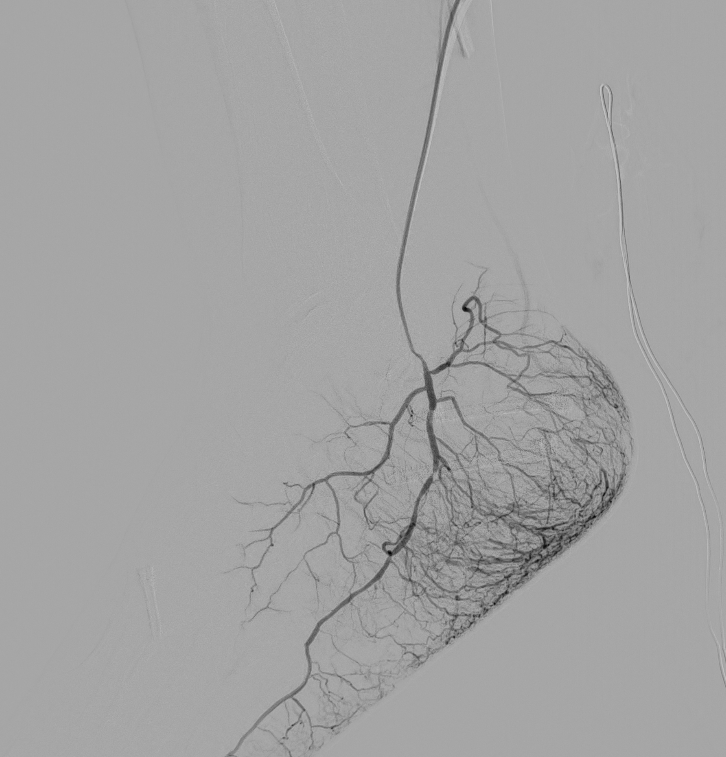

Embolisation

Embolisation refers to blocking of target blood vessels to prevent pain. The field if trans-arterial musculoskeletal embolisation (TAME) is one of the most exciting emerging fields in pain management. The best example is genicular artery embolisation which reduces knee pain and slows the progression of osteoarthritis. Other sites for embolisation include pain of the shoulders, elbows, wrists and ankle.